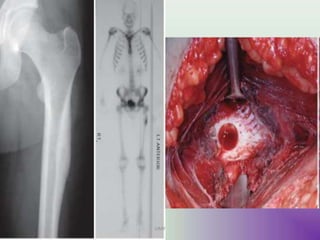

Shepherd's crook deformity

UMY

• Coxa varus angulation of the proximal femur,

classically seen in femoral involvement by fibrous

dysplasia, although may be seen in other disorders

such as Paget disese of bone and osteogenesis

imperfecta.

• The shape of the proximal femur resembles that of

the staff carried by herders (shepherds), which is

known as a crook.